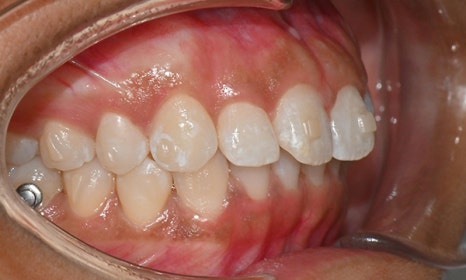

교정 마무리 후 사진 (2025.8)

교정 마무리 후 사진으로 위아래 치아 배열이 개선되었고 공간이 모두 닫혔습니다. 위아래 앞니가 깊게 물리는 과개교합도 처음에 비하여 많이 개선되었습니다. 다만 아래 작은 어금니 배열로 인하여 왼쪽 어금니 교합은 아직 완벽하지 않은 상태로, 추후 본국으로 돌아가서 자료를 transfer 해드려서 이어서 치료를 받기로 하셨습니다.

위 오른쪽 앞니의 경우 초진시에도 틀어져있던 부위의 잇몸이 내려가 있었으므로, 치아가 배열되면 좌우 잇몸 높이가 맞지 않을 것임을 미리 고지시켜드렸었고, 추후 치은성형술로 잇몸 높이를 맞추는 것이 심미적으로 더 보기 좋을 것임을 추천드렸습니다.

약 4개월의 기간 동안 처음부터 마무리까지 총 5번의 내원으로 교정치료가 마무리 되었으며, 위아래 앞니 고정식 유지장치 및 Vivera 유지장치를 착용 후 출국하셨습니다.